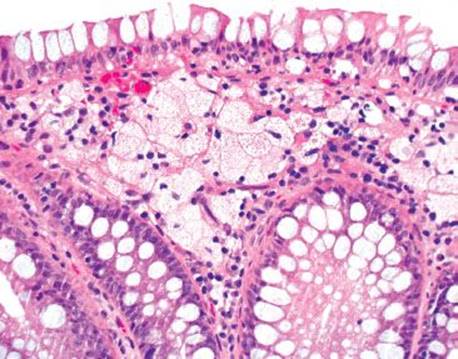

MUCIPHAGES

Azzopardi described muciphages as mucoprotein-containing macrophages in the rectum in 1966.124 The incidence was as high as 50% of rectal biopsies and no correlation with sex, age, or underlying disease was found. Academic interest in muciphages was likely borne out of the 1960s burgeoning understanding of Whipple disease, and a concern that muciphages represented Whipple disease involving the rectum. Today we know muciphages are extraordinarily common with essentially no relation to Whipple disease. A more recent study describes the muciphages as superficially located in the lamina propria and found that up to 19% present as nodules or polyps.2 These experts found a backdrop of increased chronic inflammation and mild fibrosis and suggest muciphages represent nonspecific, resolving injury. Their mucin presumably originates from “clean up” of epithelial damage or turnover (Figs. 4.263–4.269). Detailed studies show the mucin contains neutral, weakly acidic, or strongly acidic mucin with predominantly sialomucin but also a smaller component of sulfated mucin.2 The clinical importance of muciphages is simply to be aware of their benign and nonspecific nature. AFB and GMS special stains are not required upon identification because muciphages are not granulomata and have no association with infections.

Figure 4.263 Muciphages. Muciphages are benign oddities, most commonly seen in the rectum. They can be spotted at low power, as in this case.

Figure 4.264 Muciphages are mucoprotein-containing macrophages that accumulate secondary to prior rectal injury.